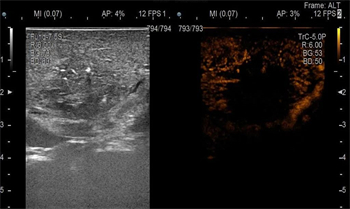

消融前术中超声检查

术中消融

消融后术中超声检查

为了追求手术根治性的最好效果,邢主任果断选择了术中微波消融的方式。超声科姜桂艳做术前超声造影检查,进行了详细的术前评估,并参与手术进行超声指导和病灶定位。